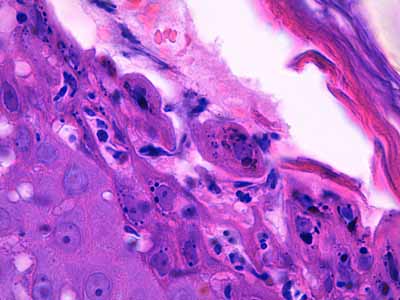

Photo 11 (Hémalun-Eosine X400) : Vue rapprochée d’une pustule intra-épidermique sous-cornée :

son toit est fragile formé de fines lamelles de kératine; son plancher épidermique

est le siège d’une forte exocytose de cellules inflammatoires; elle renferme

des granulocytes et quelques cellules épithéliales arrondies de type acantholytique.

Légendes de la Photo 11 :

- Pointes de flèche jaune : toit de la pustule intra-épidermique sous-cornée, composé de fines lamelles de kératine orthokératosique alvéolaire

- Étoile rouge évidée : cellule épithéliale acantholysée (la plus grande

- Pointes de flèche turquoise : elles délimitent le contour du plancher de la pustule intra-épidermique sous-cornée

- Flèche orange : spongiose ou œdème intercellulaire

- Étoiles vertes évidées : granulocytes dans le contenu de la pustule et en cours d’exocytose transépidermique dans le plancher épidermique

- Cercles jaunes : pustules micro-loculaires qui confluent en position sous-cornée pour former la pustule dont le plancher est matérialisé par les pointes de flèche turquoises

- Double flèche noire : épiderme

- Double flèche pointillée noire : derme